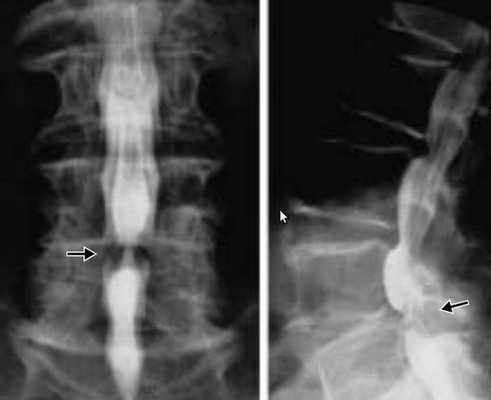

Функциональная спондилография поясничного отдела от 12.02.2019: остеохондроз II степени; спондилоартроз; нестабильность сегментов на уровне L4-L5 и L5-S1; ретролистез — смещение L5 позвонка назад — I степени. Электронейромиография (ЭНМГ) от 12.02.2019: малоберцовые нервы в норме с обеих сторон; признаки заинтересованности корешков L4-S1 справа. Мультиспиральная компьютерная томография (МСКТ) ПКОП от 13.02.2019: КТ-картина дегенеративно-дистрофических изменений поясничного отдела позвоночника; большая задняя срединная грыжа межпозвонкового диска на уровне L4-L5 позвонков с абсолютным стенозом спинального канала; задние диффузные протрузии дисков L5-S1 и умеренная протрузия уровня L2-L3. МРТ ПКОП от 14.02.2019: МР-картина дегенеративно-дистрофических изменений сегментов ПКОП; задняя медианная экструзия (выбухание) диска L4-L5 с признаками компрессии корешков конского хвоста и вторичного дурального стеноза на уровне L4-L5 на 2/3; протрузии дисков L2-L3 и L5-S1; ретролистез L5 I степени.